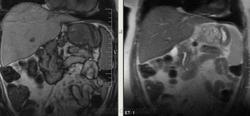

Интересные брюшные полости пошли в последнее время. Женщина, 1941 г.р. Оформлялась на операцию (по глазам), прошла УЗИ, после чего направили к нам. Жалобы только на глаза и суставы, на брюшную полость никаких. 2 года назад делала ФГС - все в порядке было. Коллеги, подскажите, пожалуйста, откуда растет эта штука? Из брюшины? Или из желудка? Или еще откуда-то?

Как-то очень близко к желудку прилежит, даже местами четко граница не прослеживается.

Может, скажу ерунду, но не от самого желудка (наружного мышечного слоя)? Ну, раз речь о панкреас и печени даже и не идет...

Согласен с Алексеем Станиславовичем. Опухоль связана со стенкой желуда, что видно на сканах 76, 77, 110, 111, стенка желудка истончена, накапливает контраст. На лейомиому в чистом виде опухоль не очень похожа, как я её себе представляю, зоны деструкции, кровоизлияния, может быть малигнизированная если. Но выглядит довольно доброкачественно в плане операбильности, имеет капсулу (не в месте контакта с желудком). Мне недавно попадалась опухоль точно такой же локализации, но имела совершенно другую структуру, прилежала к брюшине без явных признаков прорастания её. Пациентка врач, я думаю узнаю гистологию у неё, но та выглядела злокачественной.